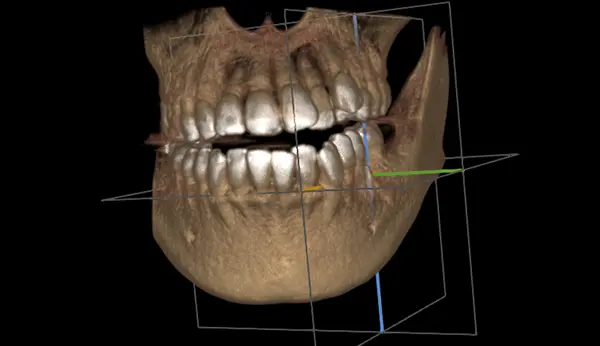

インプラント手術を受けていただく全ての患者様に、術前にC Tを撮影します。患者様の骨の形や神経・血管の走行などを正確に把握し綿密に計画を立てて、安全にインプラント処置を行います。

インプラント治療をするにはまずは現在の状態の診査が必要です。診査には視診、レントゲン診査、CTによる診査、模型による診査があります。

堺筋本町駅や本町駅すぐの歯医者はやし歯科ほんまち院の手術はコンピューターによるガイドシステムに基づき進めます。(すべての症例に用いるわけではありません)患者様に合った穴の位置・角度・深さをコンピューターで割り出し、その通りに手術をするための補助装置(サージカルガイド)を使ってインプラントを埋めるため、傷が少ないのが特徴です。局所麻酔で行い、所要時間は1時間~2時間程度です。